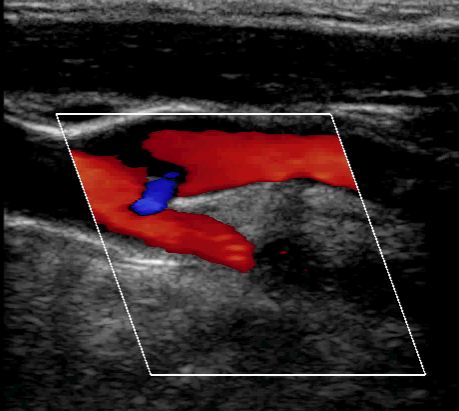

Domande su Aneurisma aortico

Buongiorno,

mio babbo in seguito ad aneurisma all'aorta ha subito un intervento dove gli hanno installato una protesi nel torace nella curva ascendente dell'aorta.

I medici hanno ipotizzato che la protesi impiantata lo scorso anno all'aorta si sia allargata o mossa e che tocchi dei nervi di bocca, gola e epiglottide e che causi questi disturbi.

chiedo io: e' possibile che una protesi artificiale all'aorta si sposti o si allarghi??? A ME SEMBRA UNA COSA ASSURDA, sto chiedendo parere anche a voi

se ho capito bene la protesi è stata impiantata 1 anno fa?! è impossibile che si sposti, fa parte integrante dell'aorta, .

E' invece possibile che vi sia un ulteriore dilatazione a monte o a valle della protesi.

Dr. Guidalberto Guidi